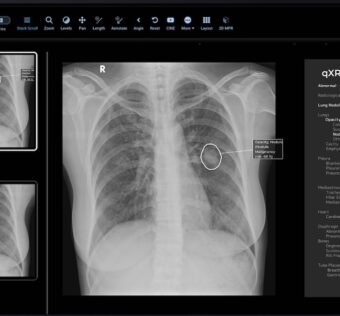

![]() Mylab leverages Qure.ai’s tech to enhance TB screening

MobiHealthNews - (Thursday February 16, 2023) Indian biotech company Mylab Discovery Solutions is integrating Qure.ai’s AI technology into its upcoming x-ray device for screening tuberculosis.According to a press statement, MyBeam is a compact, lightweight device equipped with high-frequency technology for detecting TB. It will be powered by Qure.ai’s deep-learning software qXR to analyse chest x-ray images and identify TB within a minute. ![]() Morning Headlines 2/16/23